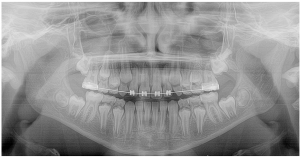

Compensação natural na Classe II

As discrepâncias esqueléticas verdadeiras, sobretudo as anteroposteriores, apresentam, na sua maioria, compensações dentárias em diversos graus. Normalmente nas Classes III de Angle observa-se uma protrusão dos incisivos superiores e a retroinclinação dos inferiores. Já nas Classes II, essa compensação apresenta-se numa relação inversa, onde os incisivos inferiores posicionam-se protruídos e os superiores retroinclinados.

Essas posições dentárias podem ser consideradas como uma tentativa natural de busca de equilíbrio entre os arcos dentários, o que pode mascarar pequenas discrepâncias esqueléticas, mas tornam-se ineficientes nas moderadas e severas. Nesses casos, um planejamento orto-cirúrgico restabelece não apenas o equilíbrio dentário, mas também o esquelético e, principalmente, o facial.